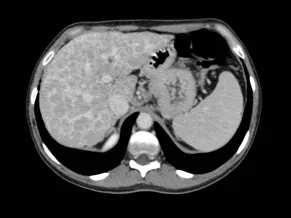

The Cirrhotic Liver: A Case-Based Review Course

This new edition of the Liver Imaging Course offers an interactive, case-based format designed to immerse participants in the real-world diagnostic process of liver imaging. Structured as a virtual reading-room experience, the course minimizes traditional lectures and mostly focuses on interpreting, discussing, and learning from clinical cases.

Cases will be carefully selected and categorized as typical, atypical, and challenging, allowing participants to progressively refine their diagnostic approach and confidence across the full spectrum of cirrhotic liver imaging.

- The cirrhotic liver: morphology and imaging features

- Focal lesions in the cirrhotic liver